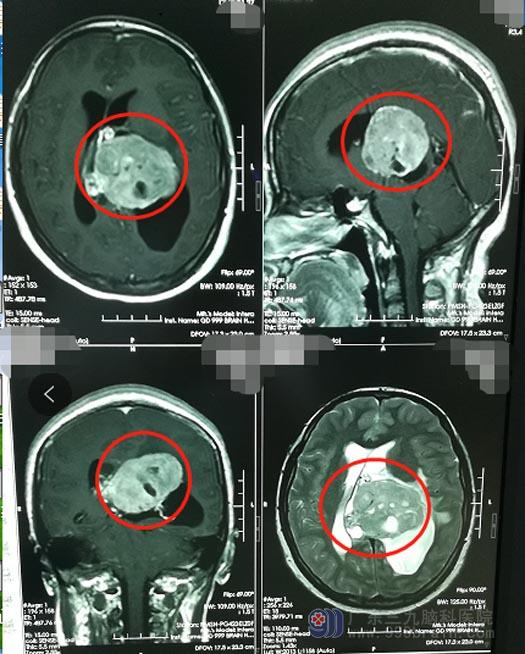

但医生的话让一家人心头一紧,“你们还是去神经外科看看吧,这应该不是心理的问题”。头颅CT检查证实了心理科医生的判断:“左侧脑室占位性病变,性质待查”。这下家人不敢马虎了,斟酌之后果断地来到了广东三九脑科医院神经外五科。主管医生对小美进行了进一步的检查,结果显示“左侧侧脑室体部占位性病变,大小约66mm×47mm×49mm”。